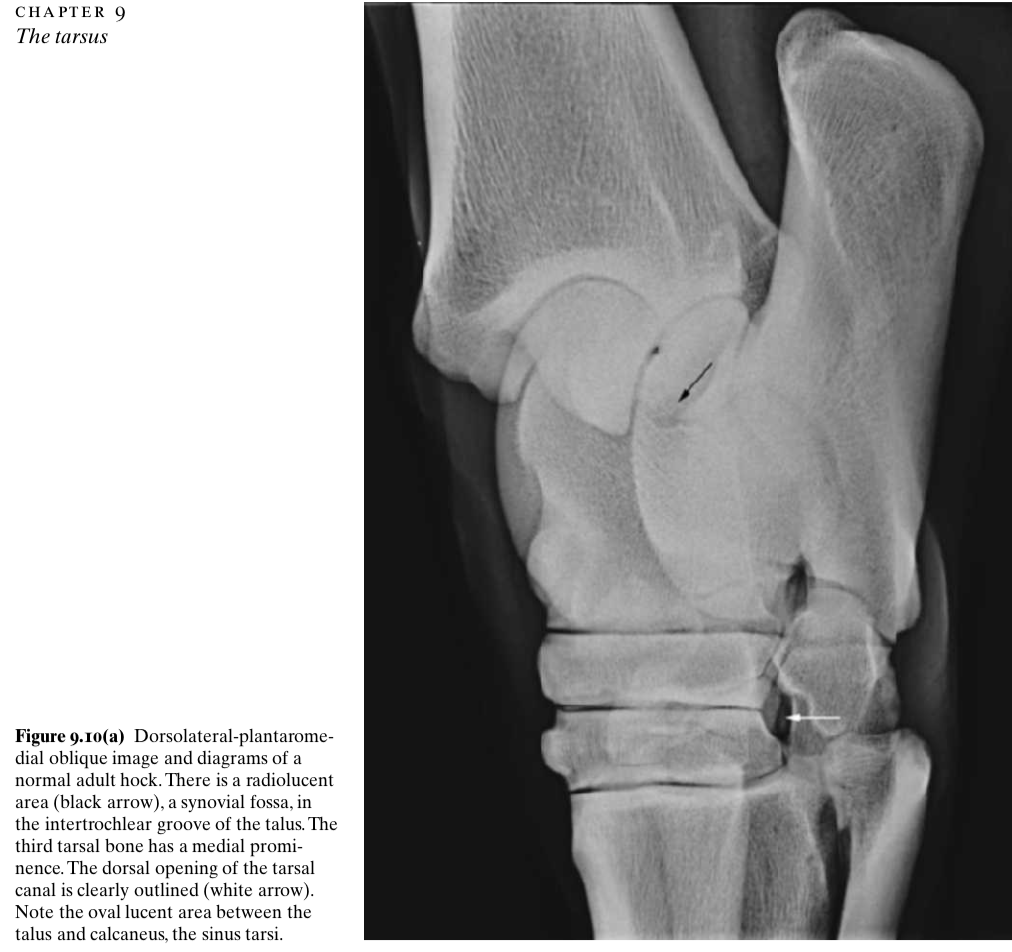

Three normal lucencies visible on a DLPMO rad

1) Synovial fossa in the intertrochlear groove of the talus proximally

2) Sinus tarsi - between talus and calcaneus platarolaterally

3) Tarsal canal between central/third and fourth tarsal bones